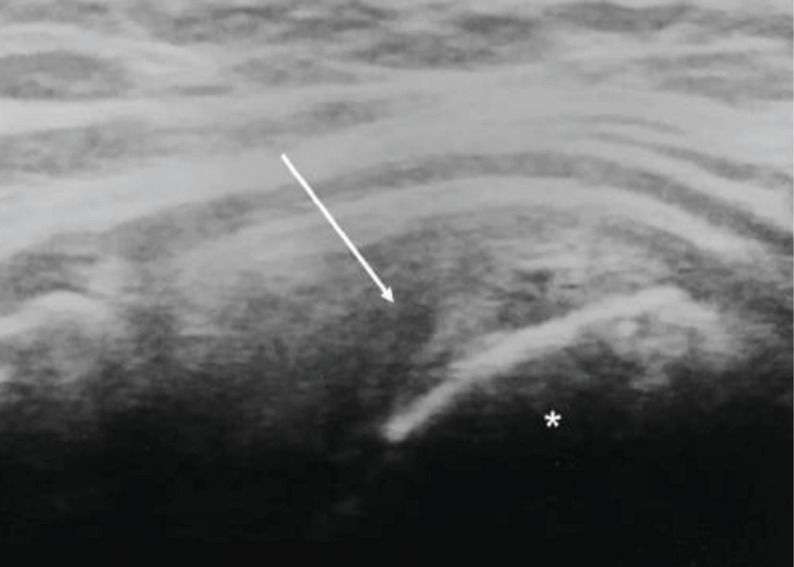

Material and methods: We retrospectively identified 27 patients who underwent antegrade intramedullary nail fixation for traumatic humeral shaft fractures and received follow-up for at least 5 years post-operatively. The patients were divided into two groups: those without tears and those with partial or complete tears, diagnosed using ultrasonography. We compared the functional and radiological shoulder outcomes between the two groups.

Results: Of the 27 patients, 10 had partial or complete supraspinatus tears with a mean follow-up of 7.5 years postoperatively. The incidence of acromial spurs was significantly higher in patients with partial or complete tears than in those without tears (P<0.001). There were no significant differences in the age and sex-adjusted Constant score, or the American Shoulder and Elbow Surgeon score between the two groups.